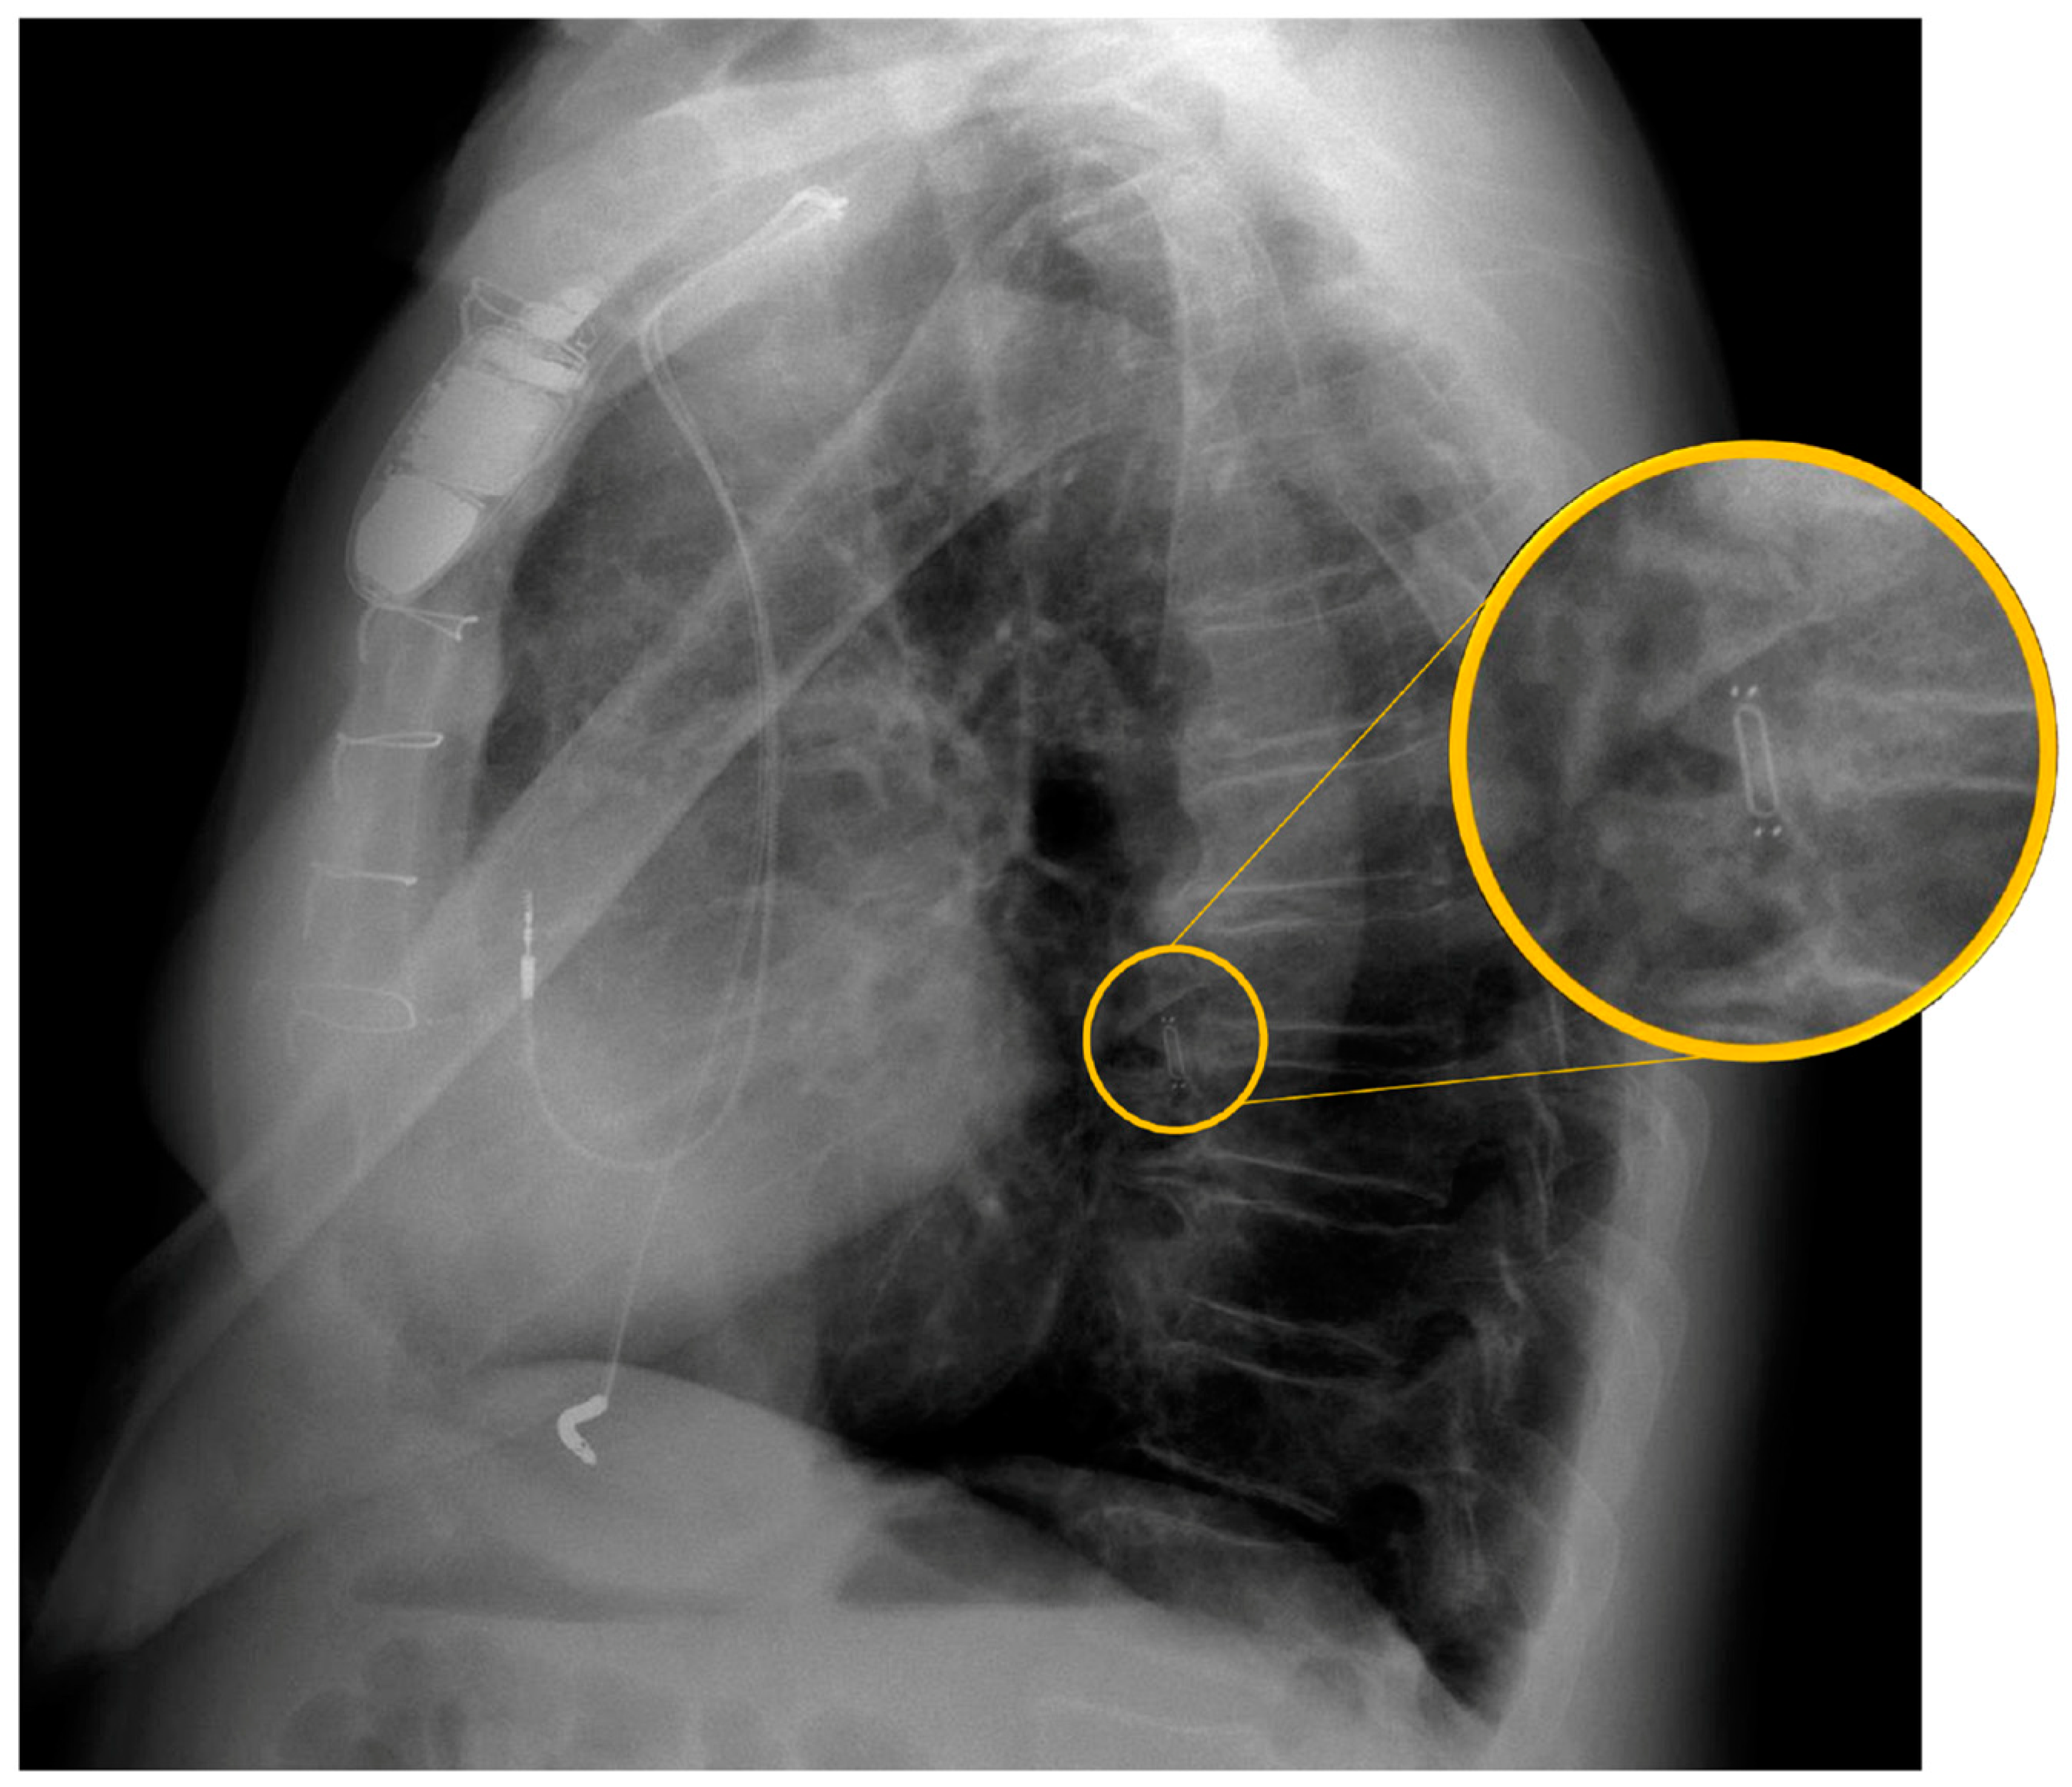

7. Implant Procedure

- Shavelle, D.; Jermyn, R. The CardioMEMS Heart Failure Sensor: A Procedural Guide for Implanting Physicians. J. Invasive Cardiol. 2016, 28, 273–279. [Google Scholar] [PubMed]